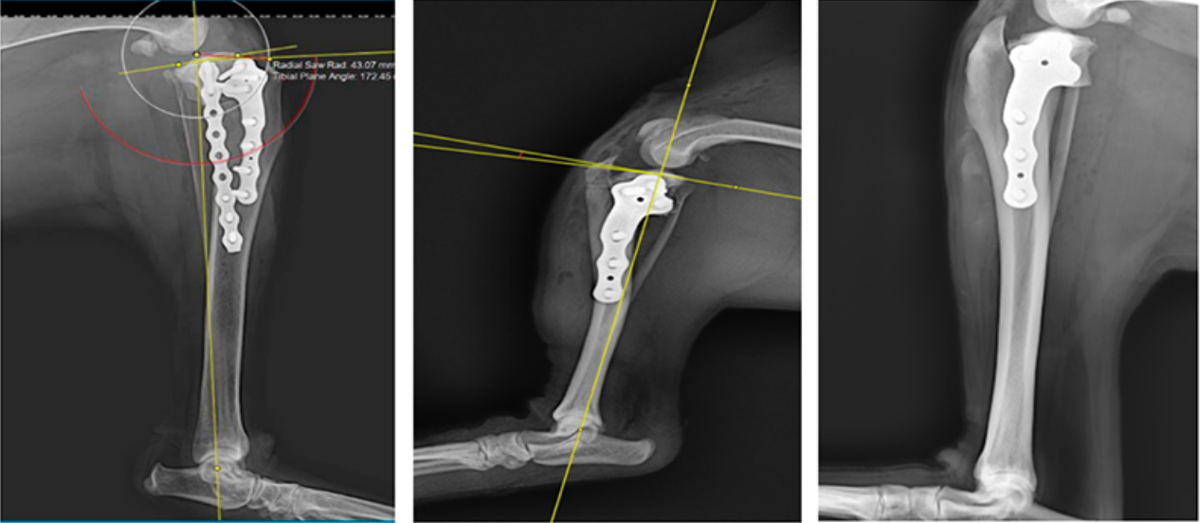

Tibial plateau leveling osteotomy (TPLO) alters the mechanical structure of the knee joint, achieving stability through active joint restraint [1.2]. Because the tibial plateau has a posterior slope, weight-bearing on the tibia in a knee with CCL rupture creates shear forces, leading to abnormal tibial motion. The goal of TPLO surgery is to create a 3-7° slope on the tibial plateau (see Figure 8) that effectively controls tibial sliding by actively restraining the posterior cruciate ligament and the knee joint (see Figures 9 and 10). TPLO is an effective surgical procedure for dogs with complete and partial CCL ruptures.